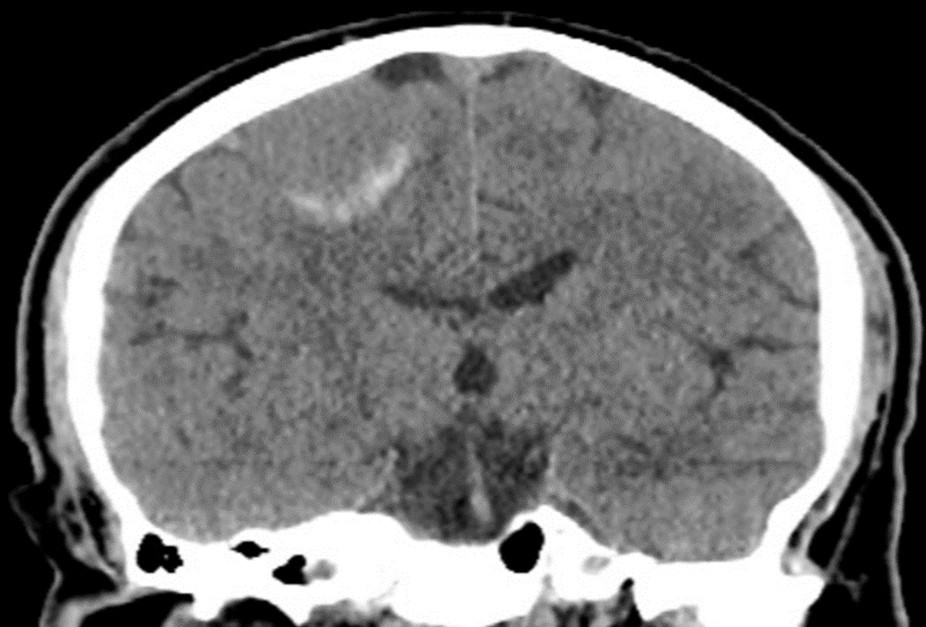

Treatment planning for LINAC-based radiosurgery has been performed by ERGO ++ (CMS, Elekta, UK) radiosurgery planning system. Optimal target coverage and normal tissue sparing has been achieved by using a single 360-degree arc, double 360-degree arcs, or five 180-degree arcs in radiosurgery planning. Synergy (Elekta, UK) LINAC available at our department has been used in delivery of treatment. Delineation of the target volume on planning CT and MR images has been optimized by selecting the appropriate windows and levels for radiosurgery planning. Sagittal and coronal images have been used in addition to the axial planning CT images to achieve accurate contouring of target volume and critical structures. Arc Modulation Optimization Algorithm (AMOA) has been utilized for optimization of target volume coverage and critical organ sparing. Figure 1 shows coronal CT image of a patient with atypical meningioma, and Figure 2 shows the corresponding coronal MR image of the same patient with atypical meningioma.

Figure 1.Coronal CT image of a patient with atypical meningioma